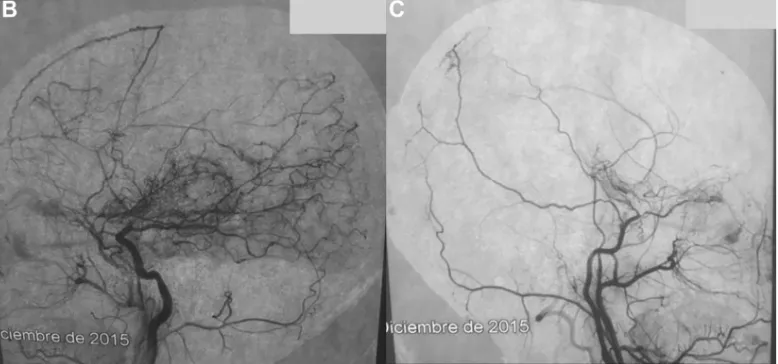

烟雾病(Moyamoya Disease),这个名字源于脑血管造影时,颅底异常血管网呈现出如同烟雾般的模糊影像。医学上,它被定义为双侧颈内动脉末端及大脑前、中动脉起始部,发生慢性进行性狭窄或闭塞,进而在颅底形成异常血管网的脑血管疾病。这些异常血管脆弱且功能异常,不仅无法为大脑提供充足血液,还如同隐藏的 “炸弹”,随时有破裂出血的风险。

在当地医院,Hobart 接受了常规检查,但并未发现明显异常。随着症状加重,家人带着他辗转多家医院,直到遇到川岛明次教授。作为 INC 国际神经外科医生集团旗下世界神经外科专家团成员,川岛教授凭借其在圣路加国际医院积累的丰富经验,详细询问了 Hobart 的病史,并安排了全面检查。脑血管造影(DSA)结果显示,Hobart 双侧大脑中动脉起始段严重狭窄,颅底出现典型的烟雾状血管网,确诊为烟雾病。

数字减影血管造影(DSA):DSA 是诊断烟雾病的 “金标准”。通过向血管内注入造影剂,动态观察血管狭窄、闭塞及侧支循环形成情况,为确诊提供准确依据。